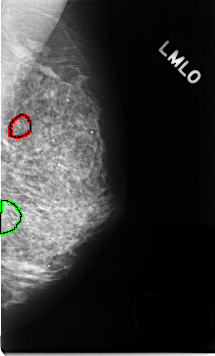

C_0344_1.LEFT_MLO

LEFT_MLO LINES 4624 PIXELS_PER_LINE 2784 BITS_PER_PIXEL 12 RESOLUTION 50 OVERLAY

FILE: C_0344_1.LEFT_MLO.OVERLAY

TOTAL_ABNORMALITIES 2

ABNORMALITY 1

LESION_TYPE CALCIFICATION TYPE PUNCTATE DISTRIBUTION CLUSTERED

ASSESSMENT 5

SUBTLETY 5

PATHOLOGY MALIGNANT

TOTAL_OUTLINES 2

BOUNDARY

ABNORMALITY 2

LESION_TYPE CALCIFICATION TYPE FINE_LINEAR_BRANCHING DISTRIBUTION CLUSTERED

TOTAL_OUTLINES 1